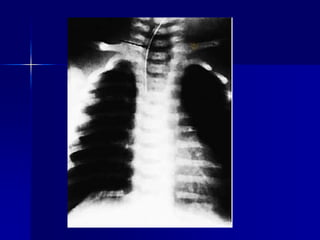

Perforación gástrica aguda en un

paciente que acude por aire

libre debajo del diafragma.

Perforación gástrica agudaen un paciente que acude por aire libre debajo del diafragma. A. Defecto mucoso con bordes limpios. B. La base de la úlcera necrótica está compuesta por tejido de granulación.